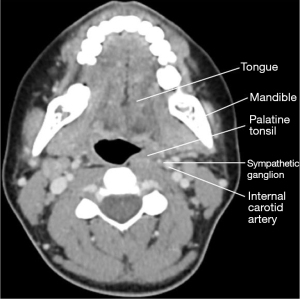

The superior cervical ganglion (SCG) is the largest and most rostral of the three cervical sympathetic ganglia, typically located at the level of the second and third cervical vertebrae (C2–C3) (18,19). It lies anterior to the longus capitis muscle, posterior to the carotid sheath, and medial to the internal carotid artery (19). This elongated structure, measuring approximately 2–3 cm, represents the fusion of the uppermost cervical sympathetic ganglia and serves as a critical relay for sympathetic innervation to the head and neck. The SCG receives preganglionic sympathetic fibers originating from the intermediolateral cell column of the spinal cord at levels T1–T3. These fibers ascend through the cervical sympathetic chain and synapse within the SCG, giving rise to multiple postganglionic pathways that influence various autonomic functions (18,19).

One of the most significant pathways involves the internal carotid nerve and plexus, through which postganglionic fibers travel alongside the internal carotid artery to supply sympathetic innervation to intracranial structures. These fibers contribute to the innervation of the eye, including the dilator pupillae muscle via the long ciliary nerves, and the lacrimal gland via the deep petrosal nerve. Dysfunction of this pathway can lead to Horner’s syndrome. Clinically, the proximity of the SCG to the palatine tonsil is particularly relevant. The postganglionic fibers, particularly those traveling along the carotid plexus and its branches, pass within approximately 1.5 cm of the palatine tonsil. This anatomical relationship may explain rare cases of sympathetic dysfunction following tonsillar procedures.

The aetiology of Horner’s syndrome in the context of tonsillectomy can be attributed to several mechanisms (18). These theories stem from the understanding of the anatomical relationship between the tonsil and the postganglionic fibres which are highlighted in Figure 2.